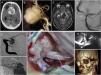

ResultadosEn el periodo de estudio, 23 pacientes con enfermedad isquémica oclusiva han sido revascularizados microquirúrgicamente. Tres pacientes presentaron complicaciones postoperatorias graves (2 hemorragias intraparenquimatosas en el postoperatorio inmediato y una trombosis de la arteria femoral). En todos los pacientes, excepto en uno, el SPECT muestra una normalización de la reserva hemodinámica cerebral (RHC). Veinte pacientes presentaron un buen resultado neurológico, sin recurrencias isquémicas del territorio revascularizado. De la serie de pacientes con moyamoya, 20 presentaban una enfermedad de moyamoya y 5 un síndrome de moyamoya con afectación unilateral. Cinco pacientes fueron tratados en edad pediátrica. Hubo un comienzo hemorrágico en 2 pacientes. El estudio de la RHC mostró un compromiso hemodinámico en todos los pacientes. El SPECT cerebral al año ha mostrado una resolución del fracaso hemodinámico en todos los pacientes. Ha habido 4 complicaciones postoperatorias (hematoma subdural agudo, 2 colecciones subdurales y una dehiscencia de la herida quirúrgica). Ningún paciente ha presentado un empeoramiento neurológico en los controles a los 6 y 12meses.

ConclusiónLa revascularización cerebral mediante la realización de una anastomosis termino-lateral entre la arteria temporal superficial y una rama cortical de la arteria cerebral media constituye una técnica indiscutible en el tratamiento de la enfermedad de moyamoya y posiblemente pueda serlo en un subgrupo de pacientes con patología oclusiva isquémica cerebral sintomática.

ResultsIn the study period, 23 patients with occlusive ischaemic disease underwent microsurgical revascularization. Three patients presented with serious postoperative complications (2 intraparenchymal haemorrhages in the immediate postoperative period and one thrombosis of the femoral artery). All patients, except one, achieved normalization of the cerebral hemodynamic reserve (CHR) in the SPECT study. Twenty patients had a good neurological result, with no ischaemic recurrence of the revascularized territory. Among patients with moyamoya, 20 had moyamoya disease and 5 had moyamoya syndrome with unilateral involvement. Five patients were treated at paediatric age. Haemorrhagic onset occurred in 2 patients. The CHR study showed hemodynamic compromise in all patients. Cerebral SPECT at one year showed resolution of the hemodynamic failure in all patients. There have been 4 postoperative complications (acute subdural hematoma, two subdural collections and one dehiscence of the surgical wound). No patient presented with neurological worsening at 6 and 12months of follow-up.

ConclusionsCerebral revascularization through end-to-side anastomosis between the superficial temporal artery and a cortical branch of the middle cerebral artery is an indisputable technique in the treatment of moyamoya disease and possibly in a subgroup of patients with symptomatic occlusive ischaemic cerebrovascular disease.